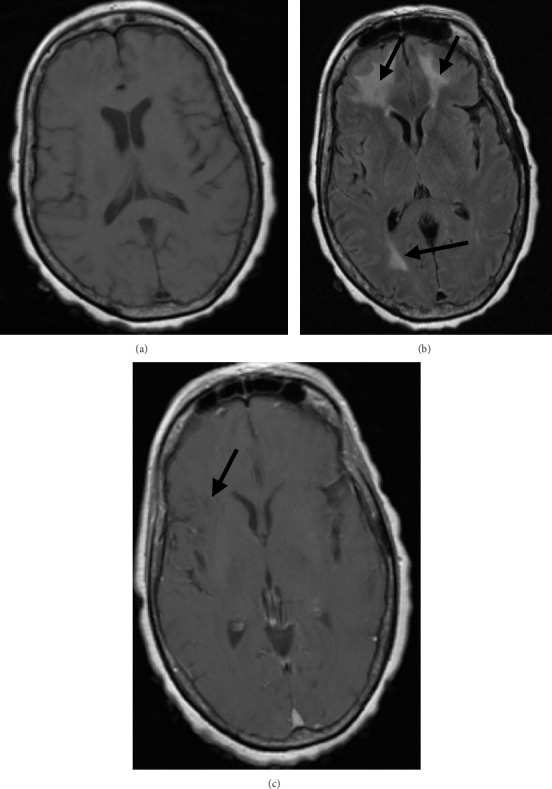

一名65岁妇女,表现为肺炎球菌败血症和脑膜炎。尽管适当的抗菌药物治疗和静脉注射地塞米松,她的精神状态没有改善。脑显像提示脑血管炎。开始大剂量静脉注射甲基强的松龙治疗后,病情迅速好转。完成3周口服泼尼松逐渐减少治疗一周后,患者的神经认知缺陷复发。更广泛的诊断评估,包括常规血管造影,再次与脑血管炎的推定诊断一致。大剂量静脉注射甲基强的松龙和较长时间的口服强的松逐渐减少导致她的疾病缓解,精神状态和左侧偏瘫有明显改善。脑血管炎是肺炎球菌性脑膜炎的一种罕见但潜在致命的并发症,可能难以识别和治疗。脑活检在诊断中的作用尚不清楚,由于其罕见性,该病的治疗缺乏确凿的循证数据。

A 65-year-old woman presented with pneumococcal sepsis and meningitis. Despite appropriate antimicrobial therapy and intravenous (IV) dexamethasone, her mental status did not improve. Findings of brain imaging were suggestive of cerebral vasculitis. Her condition improved rapidly with the initiation of high-dose IV methylprednisolone therapy. One week after completion of a 3-week oral prednisone taper, the patient's neurocognitive deficits recurred. A more extensive diagnostic evaluation, including conventional angiography, was again consistent with a presumptive diagnosis of cerebral vasculitis. High-dose IV methylprednisolone and a more prolonged taper of oral prednisone led to remission of her disease, with marked improvement in mental status and left-sided hemiparesis. Cerebral vasculitis is a rare but potentially lethal complication of pneumococcal meningitis that may be difficult to recognize and treat. The role of brain biopsy in diagnosis is unclear, and due to its rarity, management of this condition lacks conclusive evidence-based data.